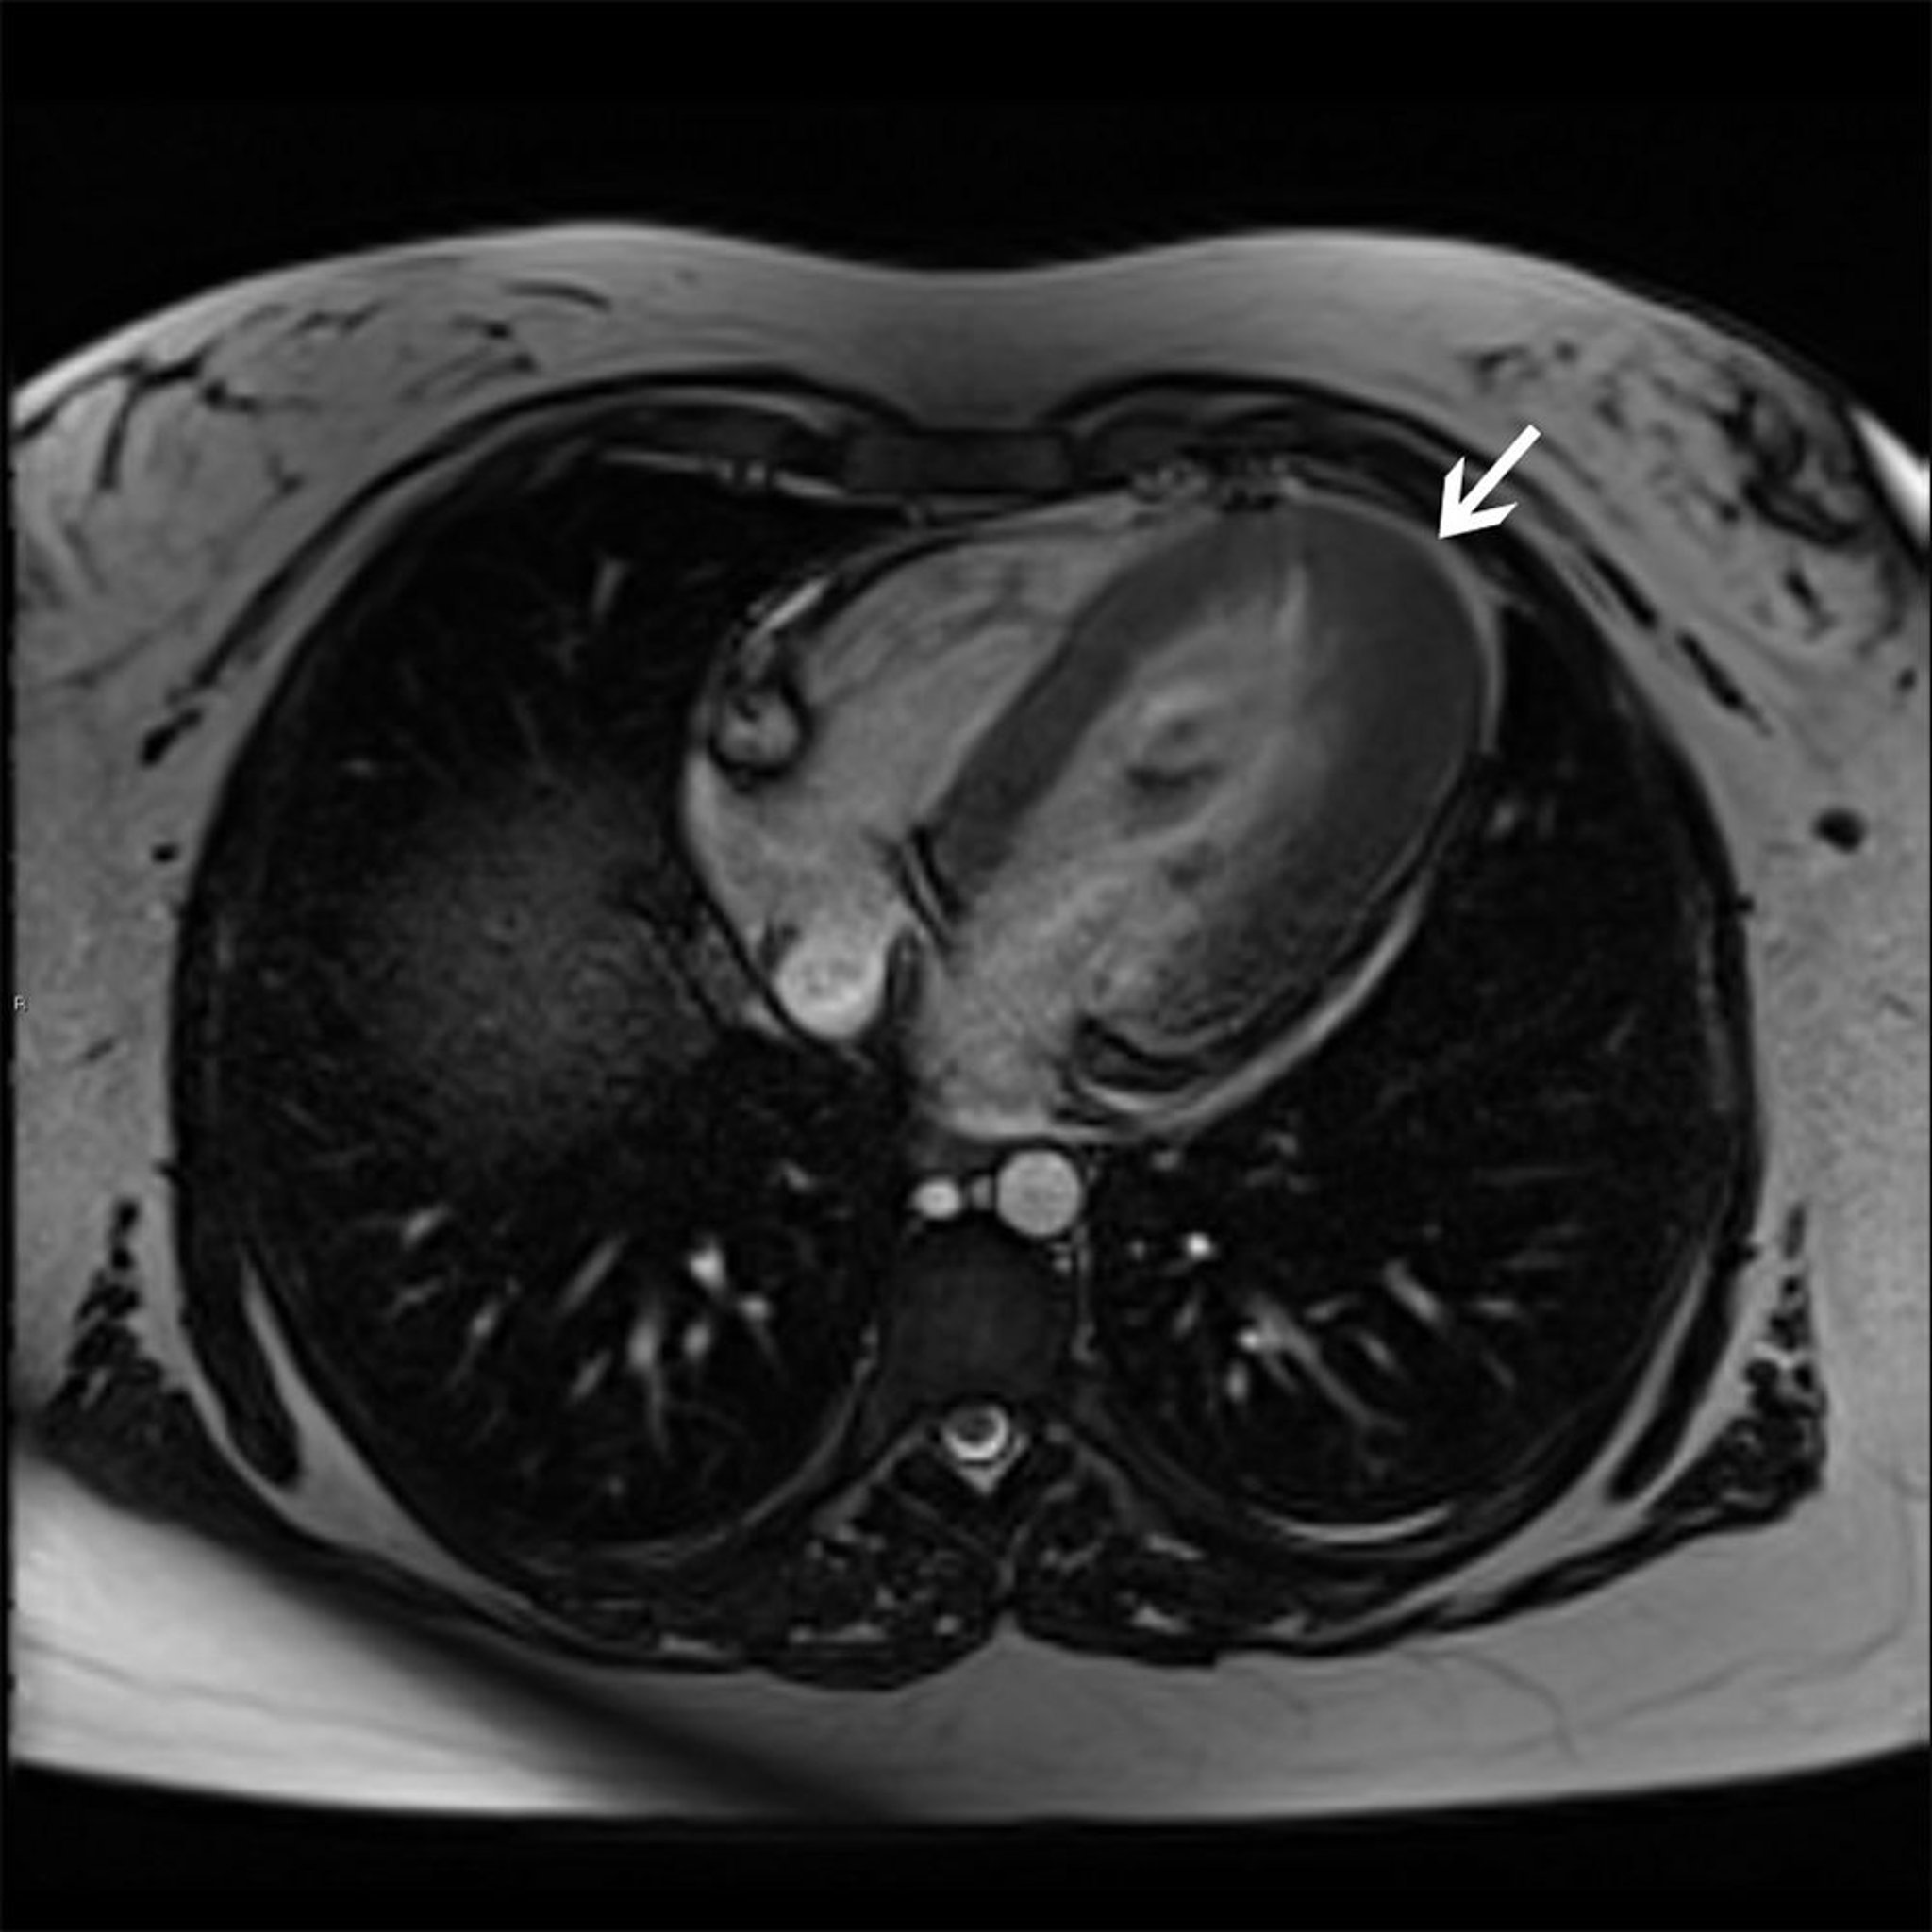

Cardiomiopatia ipertrofica (variante apicale)

Questa RM cardiaca mostra la variante ipertrofica apicale (freccia) della cardiomiopatia ipertrofica.